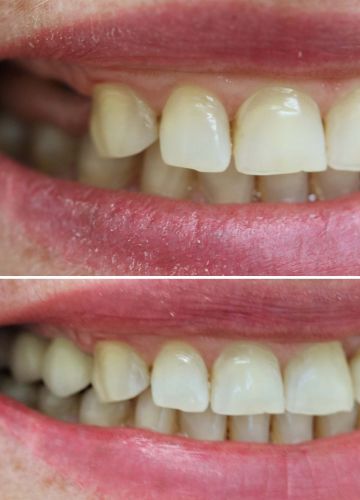

Metālkeramikas tilts + 2 zoba implanti

''Sinus lift'' un divu zobu implantu ievietošanas operācija, smaganu formētāju ievietošana

Pēc 4 mēnešiem tika izgatavots metālkeramikas tilts